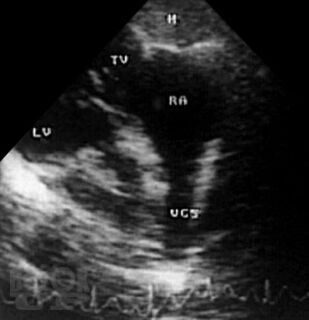

В атласе на большом числе богато иллюстрированных примеров дана эхо- и допплеркардиографическая картина врожденных пороков и ряда заболеваний сердца, а также правила применения методики ультразвукового исследования. Издание восполняет дефицит информации об ультразвуковой диагностике многих сложных врожденных пороков сердца и возможности оценки состояния больных после хирургической коррекции порока.